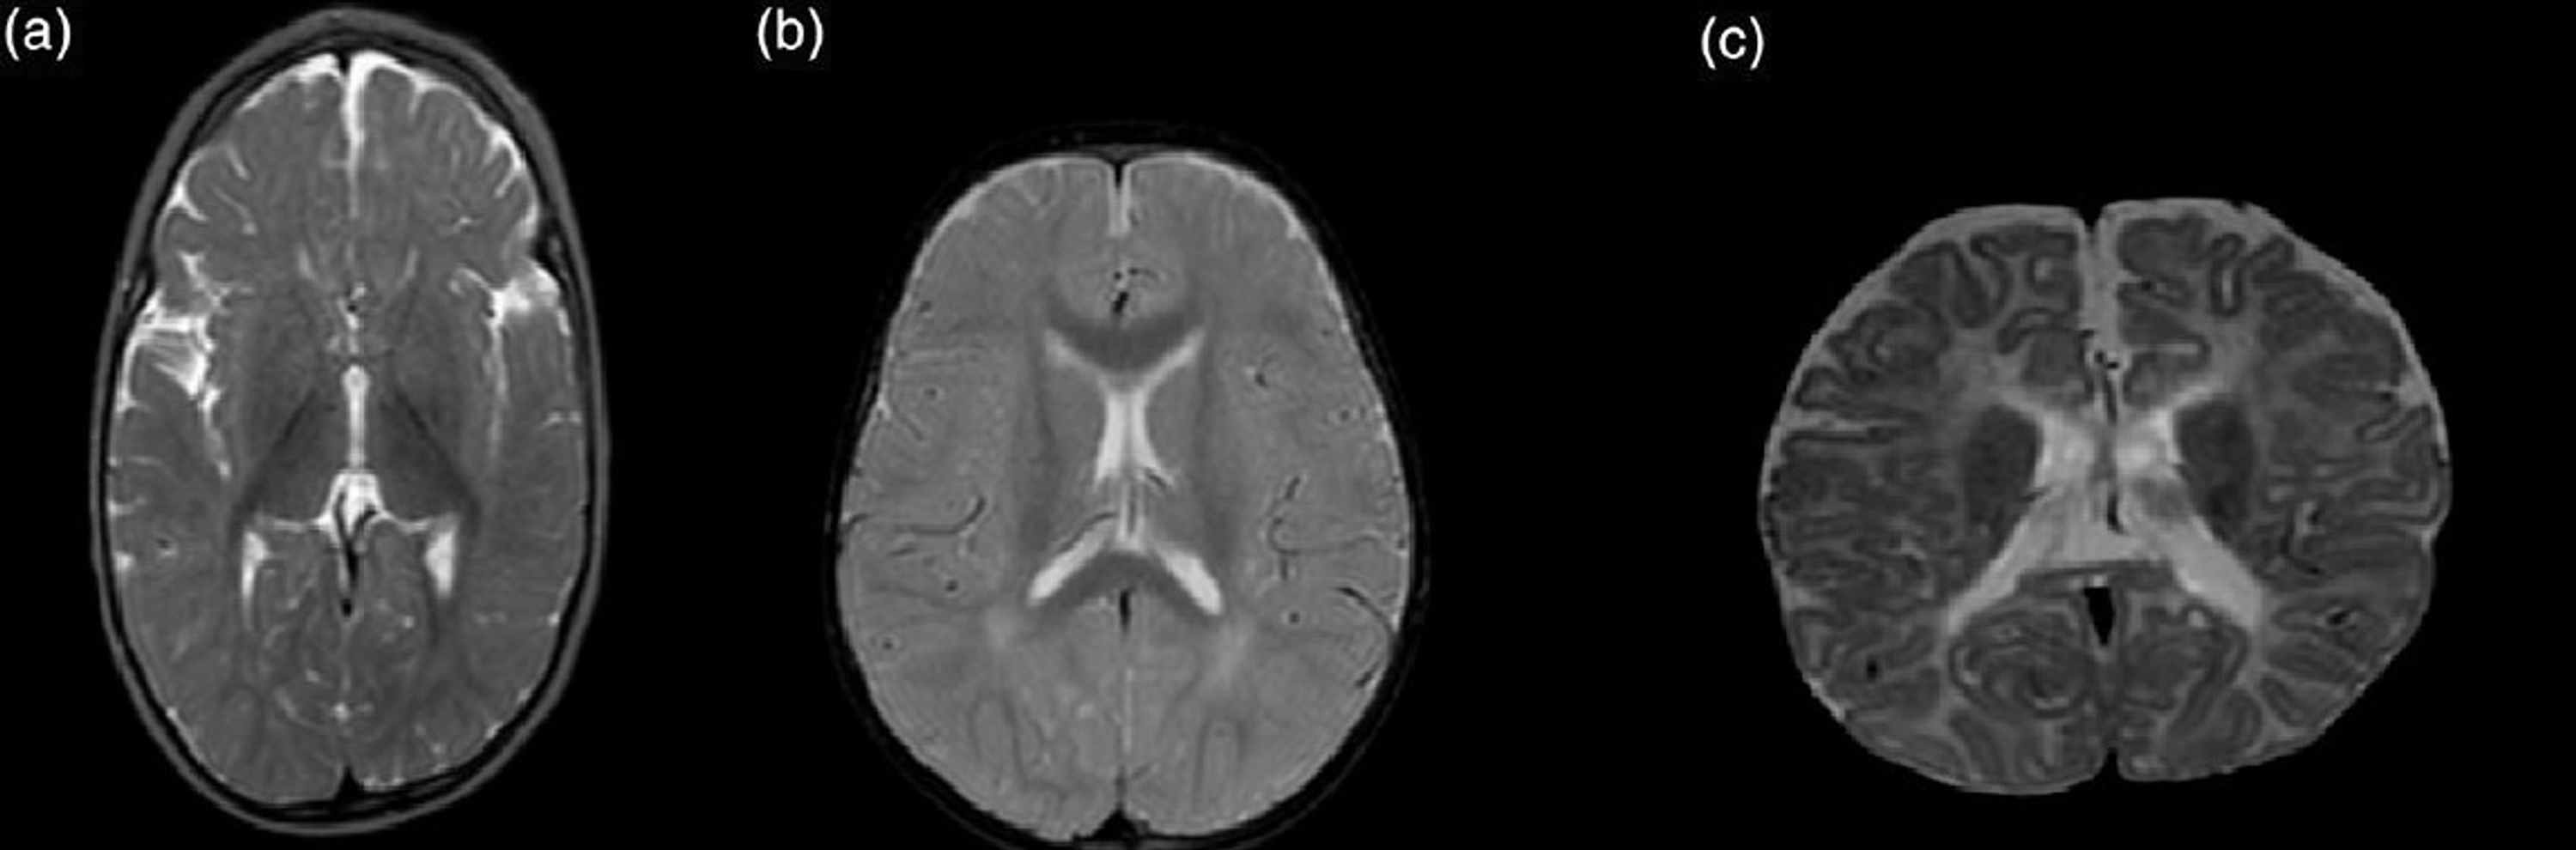

Figure 1 from Seizures as initial manifestation of vitamin Ddeficiency rickets in a 5monthold Vitamin Deficiency Seizures However, they may be able to reduce seizure activity with pyridoxine (vitamin b6) supplementation. Do vitamin deficiencies cause or worsen seizures? This usually occurs in newborns and. After detailing who it affects, it discusses its. This article provides a close look at pde. Vitamin b6 (pyridoxine) deficiency is the only type of vitamin deficiency that’s been proven to potentially cause. Vitamin Deficiency Seizures.